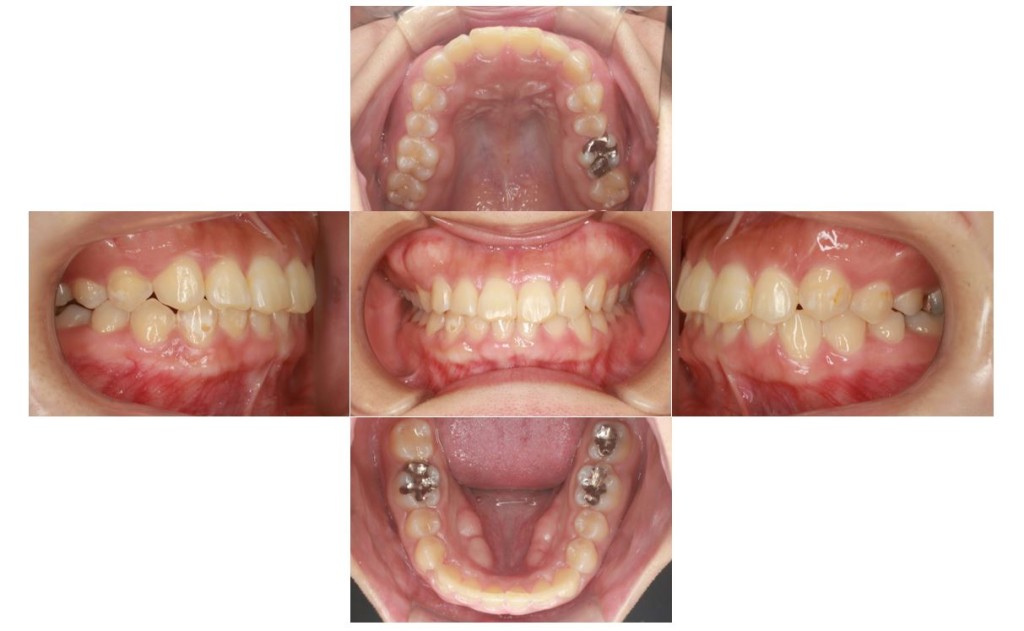

当院の症例

【1年後】

| 年齢層 | 30代 |

|---|---|

| 性別 | 男性 |

| 主訴 | ずっと気になっていた見た目、噛み合わせを含めて受け口を治したい。期間はかかってもいいので、外科手術をしないで歯列矯正だけで改善したい。 |

| 治療費用 | 検査・診断:38,500-/裏側矯正治療:1,397,000-(※全て税込) |

| 治療期間 | 3年6ヶ月40回 |

| 抜歯 | 非抜歯 |

| 矯正の装置 | 裏側矯正から治療途中に表側矯正へ変更 |

| 副作用、リスク | 歯肉退縮,歯根吸収,疼痛,咬合の違和感,装置の違和感,虫歯,歯肉炎 |